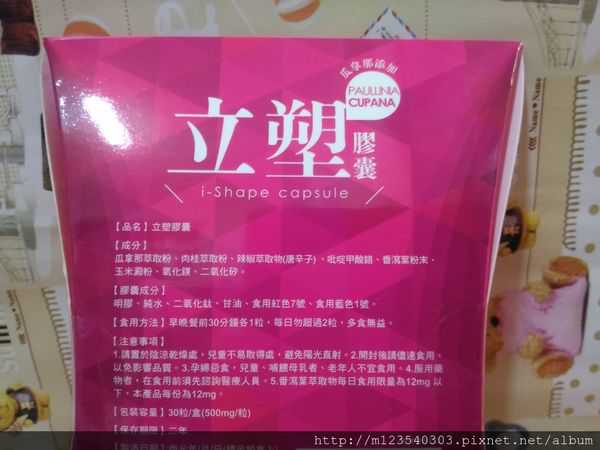

Supercut塑魔纖立塑膠囊的成分有:瓜拿那萃取粉、肉桂萃取粉、辣椒萃取物(唐辛子)、吡啶甲酸鉻、番瀉葉粉末、玉米澱粉、氧化鎂、二氧化矽。

之前上過相關課程,成分表是依照每項成分的多寡來排列順序,排在最前面的就是產品的主要成分!

那我就跟大家分享瓜拿那萃取粉、肉桂萃取粉和辣椒萃取物吧

瓜拿那萃取和辣椒萃取是可以幫助纖體瘦身常見的營養素!

1.「瓜拿那」是原產於亞馬遜流域的一種藤蔓植物,富含酵素可以幫助排便順暢,並且能抑制脂肪分解酵素,此外也有降低食慾的效果喔~~萃取物中含有天然咖啡因,可以提高新陳代謝率以及排出多餘水分!

2.「辣椒萃取物」則是可以幫助體內脂肪燃燒、增加卡路里的消耗,達到防止脂肪積聚的效果

3.「肉桂萃取物」看到肉桂,就想到麥當勞的蘋果派或是手掌麵包,雖然很多人很害怕那味道,但艾哥愛死肉桂了!!!!肉桂在古代被視為是最有價值的東方香料之ㄧ,中世紀時,肉桂的聲望僅次於昂貴的黑胡椒,除了香料和薰香價值, 傳統上肉也被用來治療消化不良、脹氣、關節疼痛、出血和經痛,研究也指出肉桂可以促進新陳代謝喔

食用方式:早晚餐前30分鐘各1粒,每日不超過2粒。(多食無益)

番瀉葉萃取物每日食用限量為12mg以下,

番瀉葉萃取物每日食用限量為12mg以下,